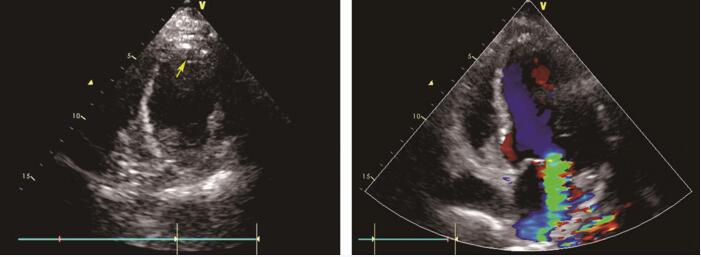

超声心动图 (1月4日):左心室各室壁运动均减弱,以前间隔、左心室前壁尤为明显;主动脉升部增宽,主动脉瓣回声增强伴反流 (+);二尖瓣对合不良伴反流 (+++~++++);左心房增大,左心室增大(左心室舒张末期内径6.35cm;舒张末容积171ml),左心室收缩、舒张功能降低,左心射血分数33%(图89-1)。

图89-1 入院超声心动图